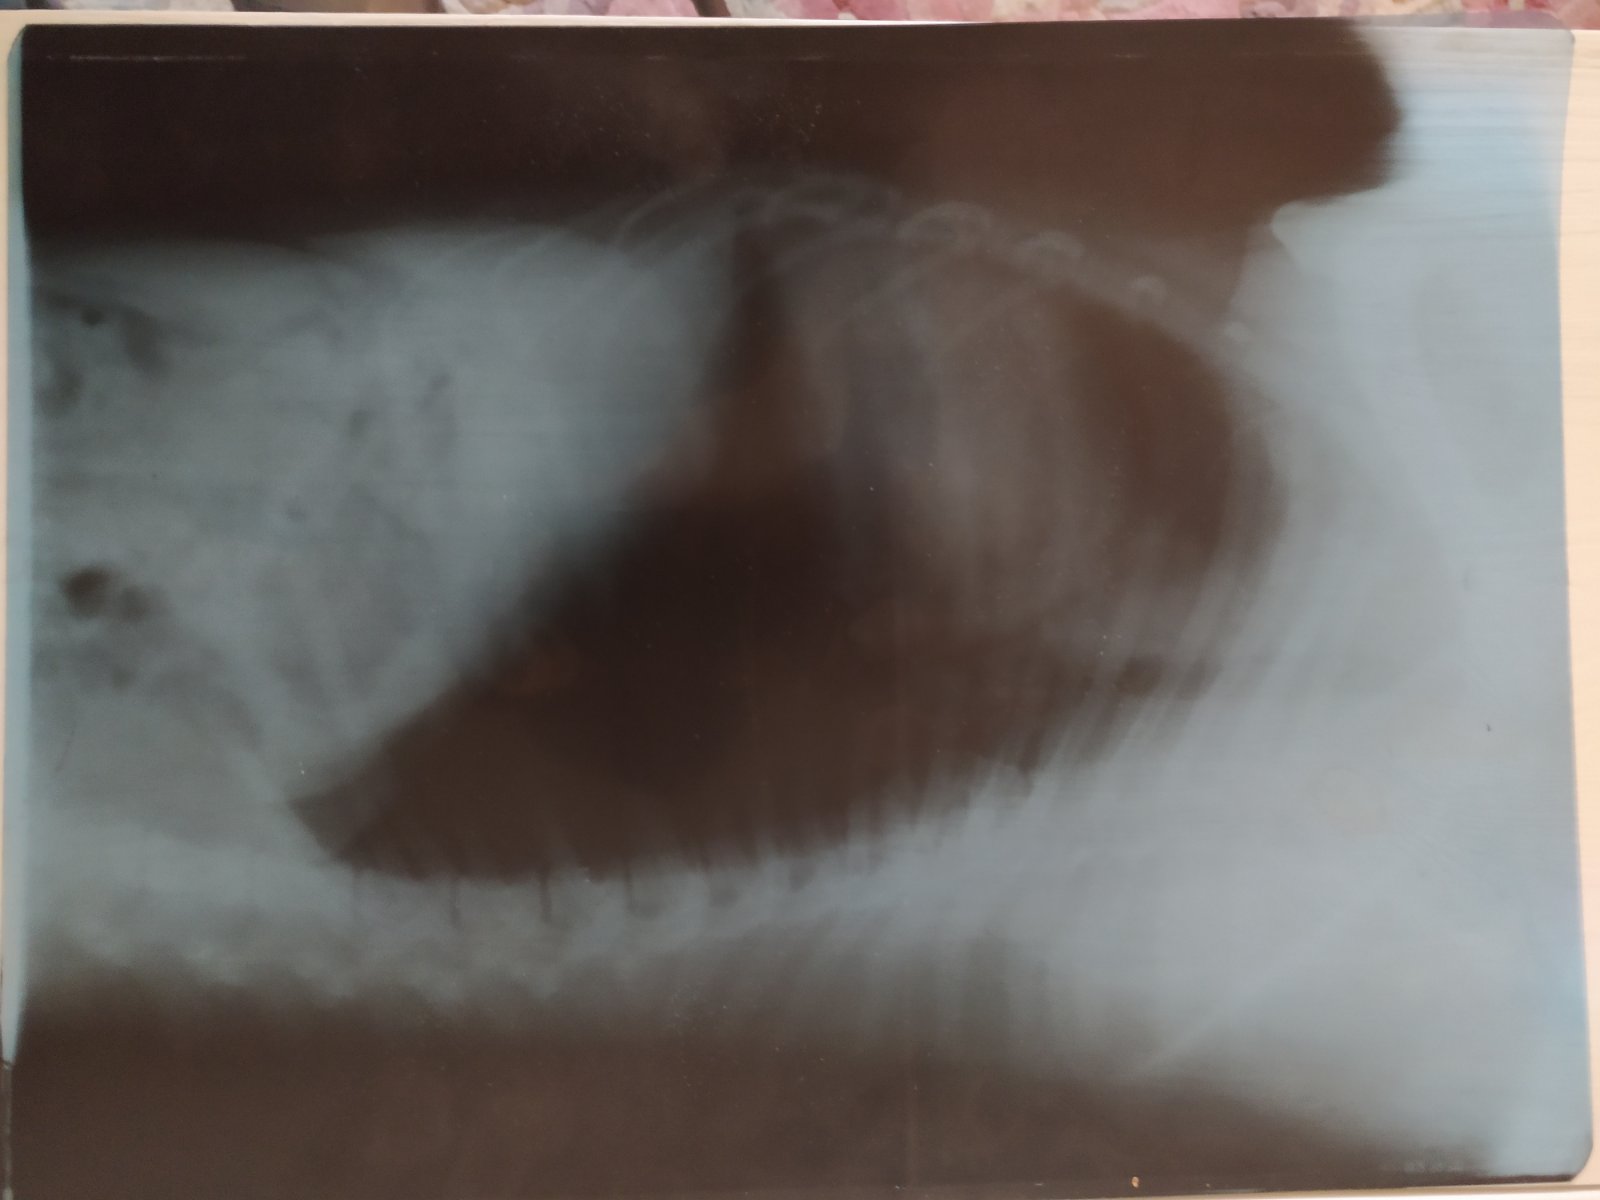

Оля с Максом были два дня назад у ветеринара на осмотре,снимок сделали,есть воспаление,оплатили только рентрен,и лекарства. Завтра общий и биохимию сдадут,потом уже по результатам глистогонить будет.Ветеринар шнауцерист,поэтому лояльно к нам.Спасибо!Подробнее Оля напишет сама.

У Макса бронхит, правильно понимаю?

Сделали парню рентген грудной клетки, УЗИ мочеполовой, биохимию и общий мочи. По результатам имеем воспаление легких, цистит, полип в мочевом и небольшой панкреатит. Также на рентгене обнаружили след давней травмы позвоночника - что-то вроде костной мозоли в районе лопаток. Дискомфорта не доставляет, на поведении вроде не сказывается, но требует осторожного обращения со спиной в некоторых ситуациях, ну и брать метровые барьеры собаке не рекомендуется.